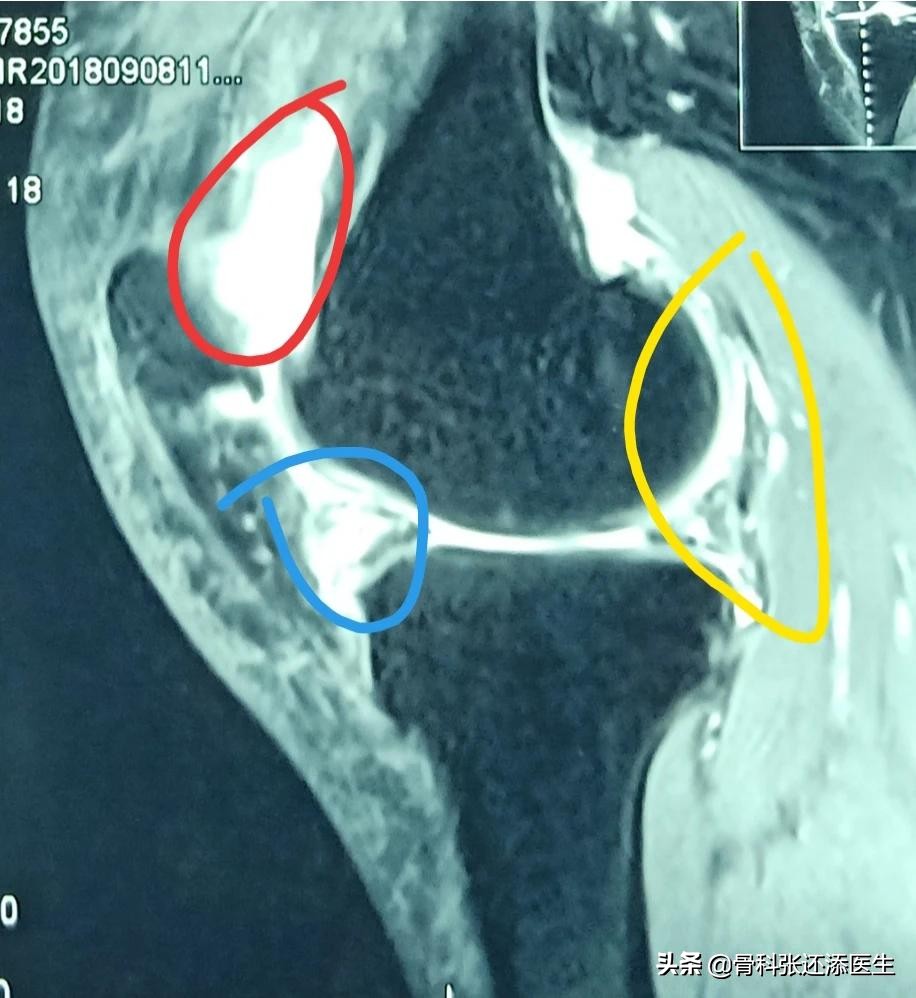

通过核磁共振或者彩超,可以较准确、较敏感地发现关节液的分布。关节液假如在量的层面没明显增加,但在影像学上的分布位置不对,也属于“积液范畴”。

膝关节是人体滑膜最多,关节面最大最复杂的关节。半月板损伤,韧带损伤等原因,和骨关节炎继发性滑膜炎,都会导致滑膜炎的产生。其次就是踝关节扭伤等,也比较常见。

很多时候滑膜炎多因急性创伤和慢性损伤所致,如膝关节扭伤、半月板损伤、侧副韧带或交叉韧带损伤等等,这个时候关节内积液增加(有淤血成分),表现为急性膝关节炎的滑膜炎。

大部分老年人的滑膜炎是因软骨退变与骨质增生产生的机械性生物化学性刺激,继发滑膜水肿、渗出和积液等。这个时候,软骨的退变可以是主因。患者往往有最近过度爬山、过度暴走等病史,结合起来有助于明确诊断。

3.另外呢,关节内游离体(关节内的废物,如骨赘,损伤脱离的半月板碎片等)也可以是主因。这个时候患者走路可能有卡压,“积液”是因为游离体在关节腔游动,加剧磨损及积液产生导致。